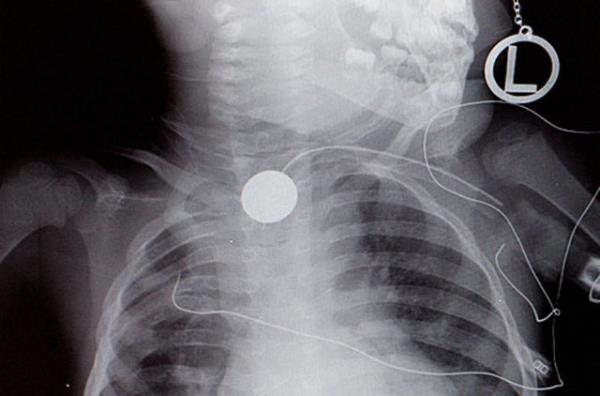

1. Hindistan'da nehir kenarında arkadaşlarıyla oynayan 12 yaşındaki Anil Barela isimli çocuk, 9 santimetre büyüklüğünde bir balık yuttu.

Hindistan'da nehir kenarında arkadaşlarıyla oynayan 12 yaşındaki Anil Barela isimli çocuk, 9 santimetre büyüklüğünde bir balık yuttu.

2. Balığın sürekli hareket etmesi nedeniyle nefes almakta güçlük yaşamaya başlayan çocuğun kanındaki oksijen oranının da ciddi oranda düşüş göstermesi sonucunda çocuk x-ray cihazından geçirildi.

Balığın sürekli hareket etmesi nedeniyle nefes almakta güçlük yaşamaya başlayan çocuğun kanındaki oksijen oranının da ciddi oranda düşüş göstermesi sonucunda çocuk x-ray cihazından geçirildi.

3. Çekimlerde ciğerlerinde dolaşan balık tespit edilince çocuk hemen ameliyata alındı. Yaklaşık 45 dakikalık operasyonun ardından balık, canlı olarak çıkarıldı. Göğüs hastalıkları uzmanı Doktor Pramod Jhawar, 20 yıllık doktorluk hayatı süresince ilk kez böyle bir durumla karşılaştığını kaydetti.

Çekimlerde ciğerlerinde dolaşan balık tespit edilince çocuk hemen ameliyata alındı. Yaklaşık 45 dakikalık operasyonun ardından balık, canlı olarak çıkarıldı. Göğüs hastalıkları uzmanı Doktor Pramod Jhawar, 20 yıllık doktorluk hayatı süresince ilk kez böyle bir durumla karşılaştığını kaydetti.